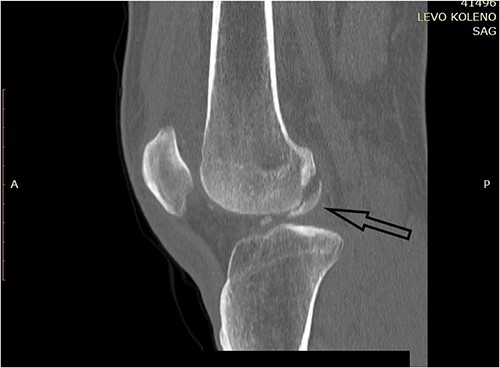

A plain X-ray of the left knee revealed a single defect of the lateral femoral condyle in the anteroposterior (AP) view. The lateral view showed a free bone fragment with a defect (Fig. 1A and B). Additional diagnostic imaging was performed. A computerized tomography (CT) scan revealed multifragmentary (three fragments) fracture of the lateral femoral condyle accompanied by a fracture of the left patella (Fig. 2). The fracture was classified as 33B3.2 according to the Association for Osteosynthesis–Orthopaedic Trauma Association (AO/OTA), Type II C (according to Letenneur) [2]. It was decided that single-approach surgery (posterior or anterior) would be insufficient for acceptable anatomic reduction and proper fixation of all the fragments because of the fracture complexity. The preoperative plan consisted of a posterior-first approach (extended posterior approach to the proximal tibia) for fixation of the largest (posterior) fragment (Fig. 3) followed by an arthroscopic anterior approach (for anterior fragment fixation). The predetermined time interval between the two procedures was to allow the healing of the joint capsule after the index surgery. Operative fixation of the patellar fracture was not indicated.

CT scan of the left knee (sagittal) focusing on the largest posterior fragment (arrow).